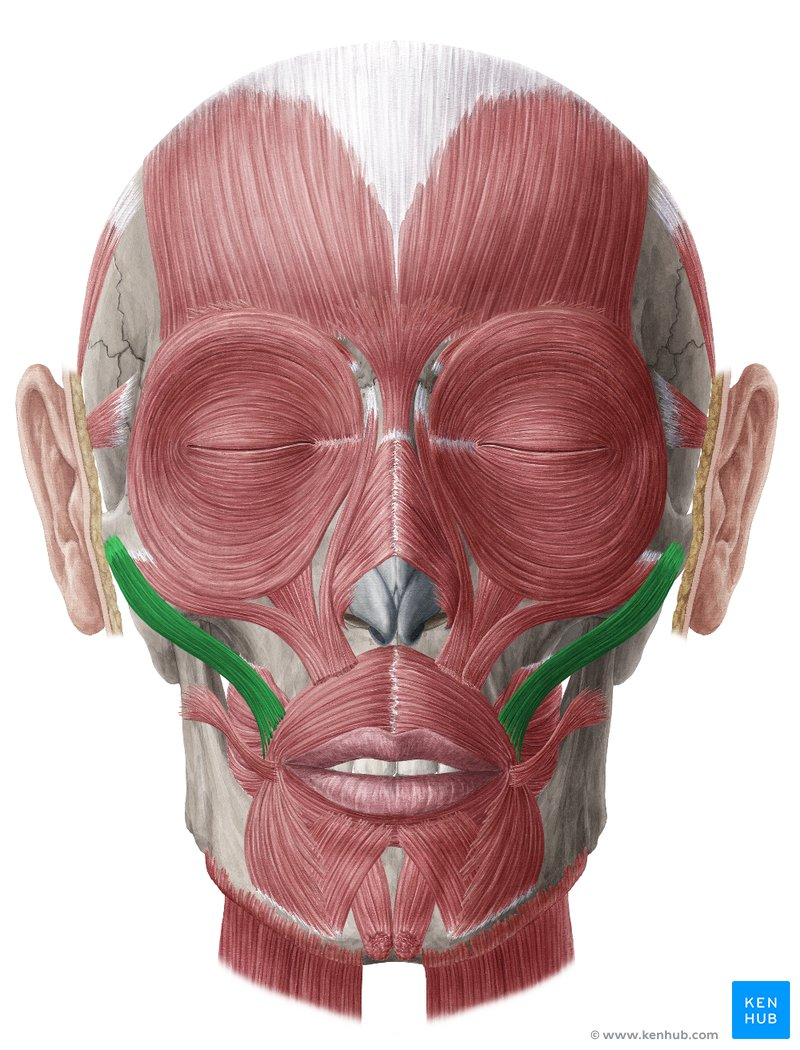

m zygomaticus

Höjer mungiporna